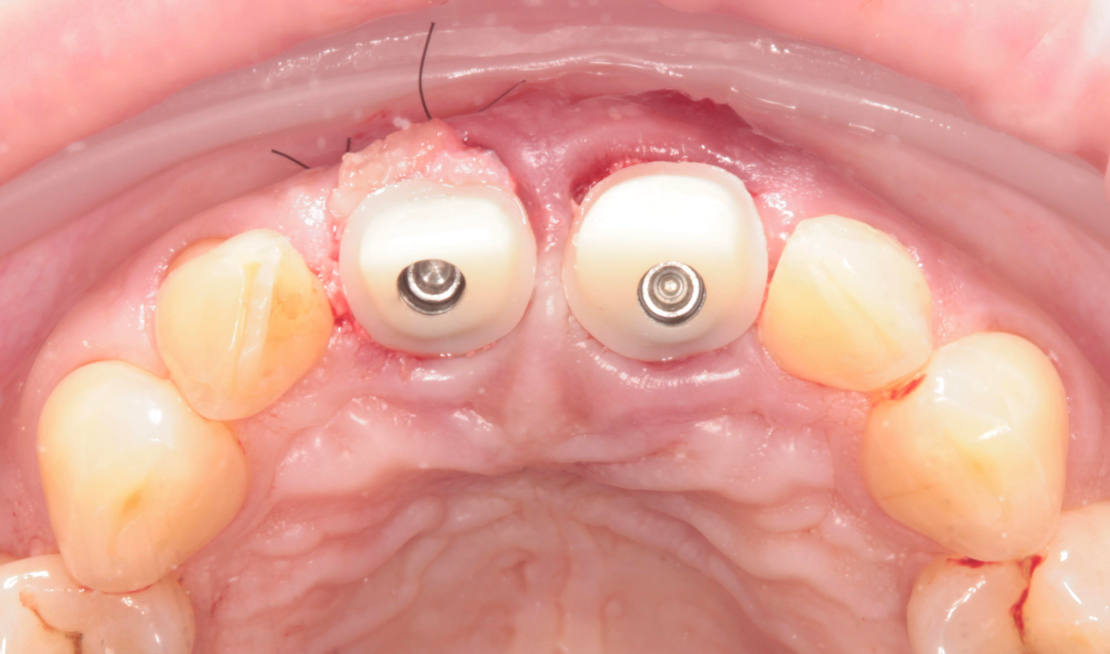

Následne sme použili protokol vŕtania a zavedenia implantátov cez šablónu (obr. 7, 8), na ktorej sme mali orientačné body pre správne napolohovanie implantátov, abutmentov a koruniek (obr. 9–14).